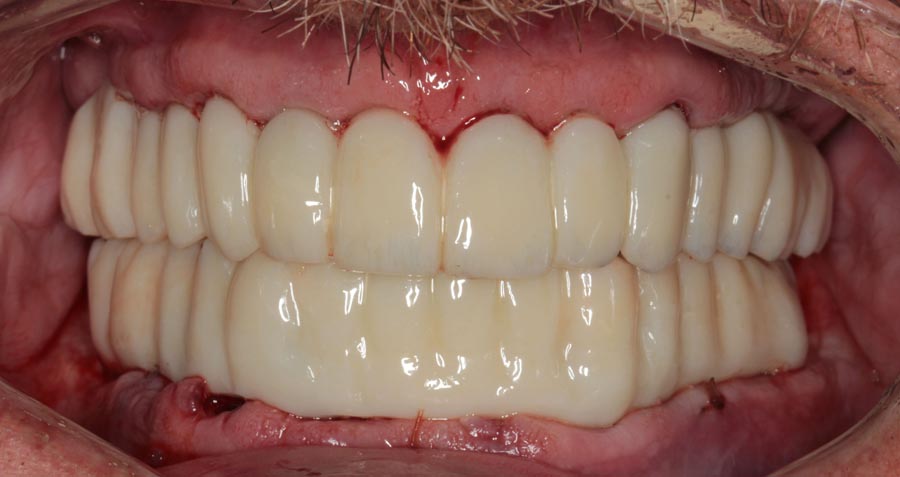

Smile GalleryImplant RestorationsFull Mouth Implant Restoration 1 of 13 Pre-operative smile Pre-operative smile Pre-operative frontal view, lips retracted Pre-operative panoramic image (note bone levels) Post-surgical panoramic image Surgical temporary bridge (note convex contours) Delivery of surgical temporary bridges in both upper and lower Two weeks post-op surgery and temporaries (note amazing tissue response) Three months post- surgery. (Note tissue development) Definitive implant bridges (FP-2) Post-treatment panoramic image Final result smile Final result smile